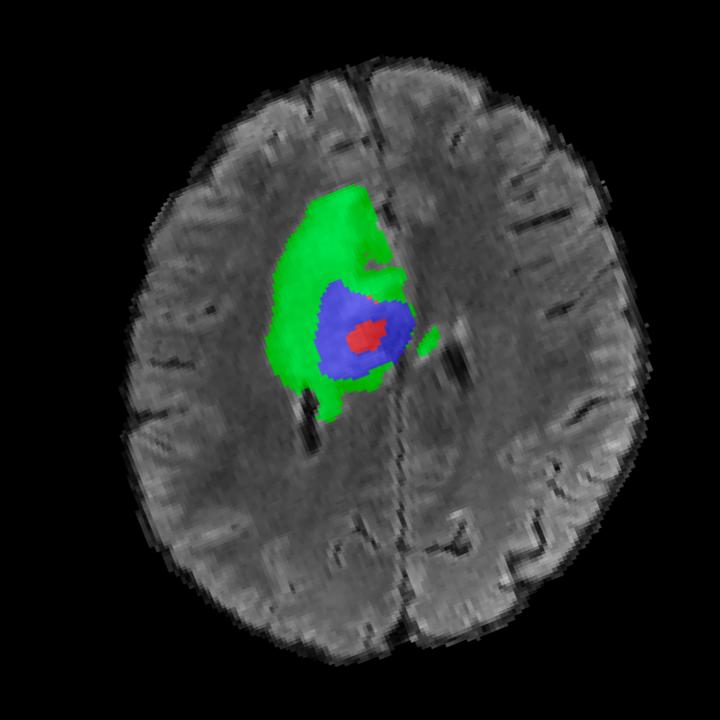

Tumour Information Preservation. For the brain tumor segmentation, we use a Swin UNETR model[27, 70], trained with random rotation, and intensity as data augmentation. In Figure 5, we highlight the tumor profiles of the generated MRIs compared to the ground truth tumour profile. In the test set with human ground-truth annotations (), the real MRI Dice score is 85.15 while the generated MRIs from a single slice have a dice score of 83.09. This shows how the generated MRIs indeed preserve the tumor information and can act as an affordable and informative pseudo-MRI, before conducting an actual costly MRI examination in hospitals.

B.4 Tumour Information Preservation

On the test set with human ground-truth annotations (), the brain volumes generated from single slice input preserve the volume of the different tumour components (paired t-test, for all 3 classes) (see Table 3). The real MRI Dice scores are put for reference to our generated MRIs. X-Diffusion outperforms baselines TPDM [36] and ScoreMRI [18] in tumour preservation (see Table 3 and Figure 12). We ran experiments comparing the tumour segmentation Dice Score varying X-Diffusion configurations. The multi-slice input X-Diffusion achieves a marginally better Dice Score than the single-slice input model (83.47 83.09). We also ran experiments with slice input used for volume reconstruction intersecting or not with tumour. We observe on average a drop of 6% Dice Score (see Table 3). Further away from the tumour the input slice for volume reconstruction is selected, and we observe a linear decrease in tumour segmentation Dice Score with the lowest value of 77.21 Dice Score (see Figure 15).

| Test Dice Score | |||||

|---|---|---|---|---|---|

| X-Diffusion Generated MRIs | ET | WT | TC | Average Dice | 3D PSNR(dB) |

| single slice | 75.48 | 89.24 | 84.57 | 83.09 | 35.81 |

| multi-slice | 75.82 | 89.56 | 85.04 | 83.47 | 36.13 |

| multi-slice (only-tumour) | 76.12 | 90.04 | 85.87 | 84.01 | 36.98 |

| multi-slice (no-tumour) | 70.14 | 84.29 | 81.65 | 78.69 | 33.24 |

| Real | 76.47 | 91.13 | 86.24 | 85.15 | N/A |